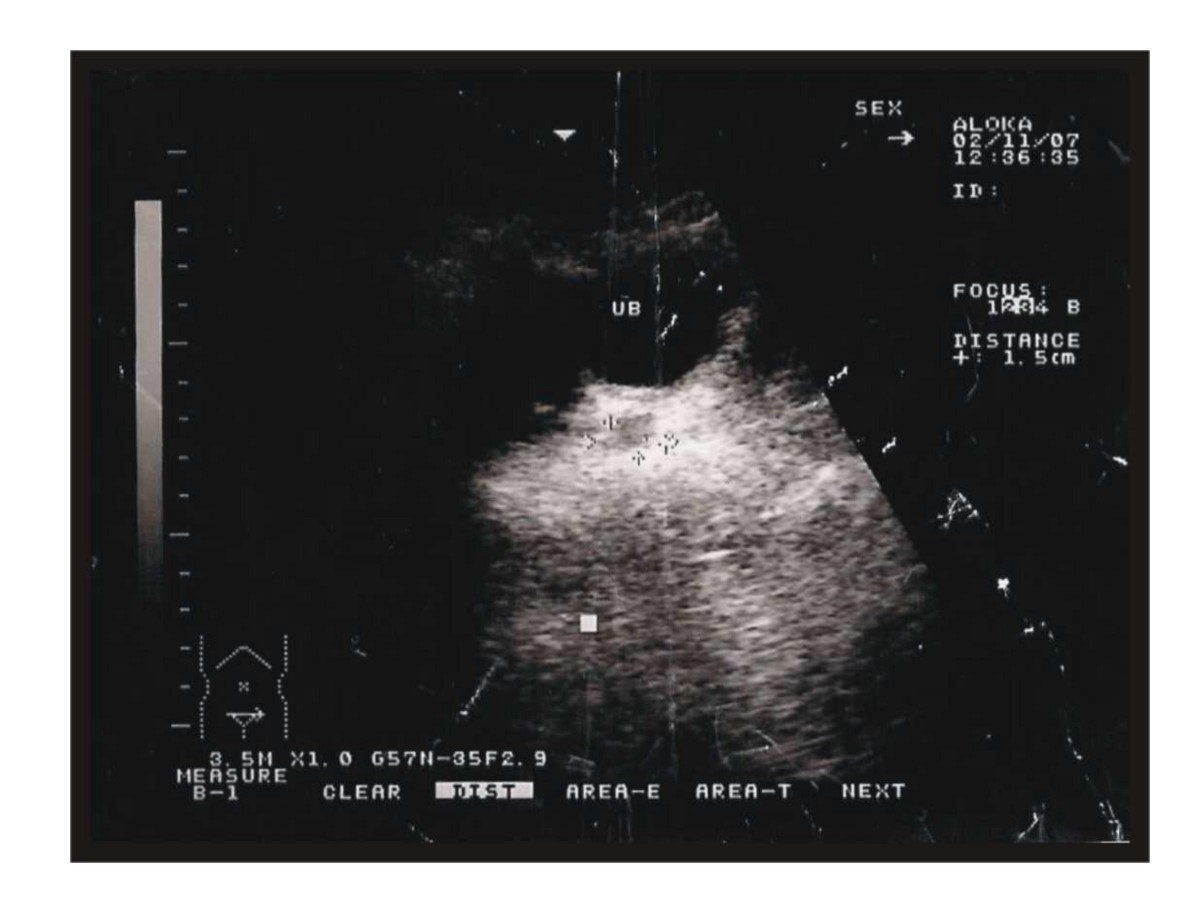

Figure 4

Ultra sound showing a mass in the prostate's position.